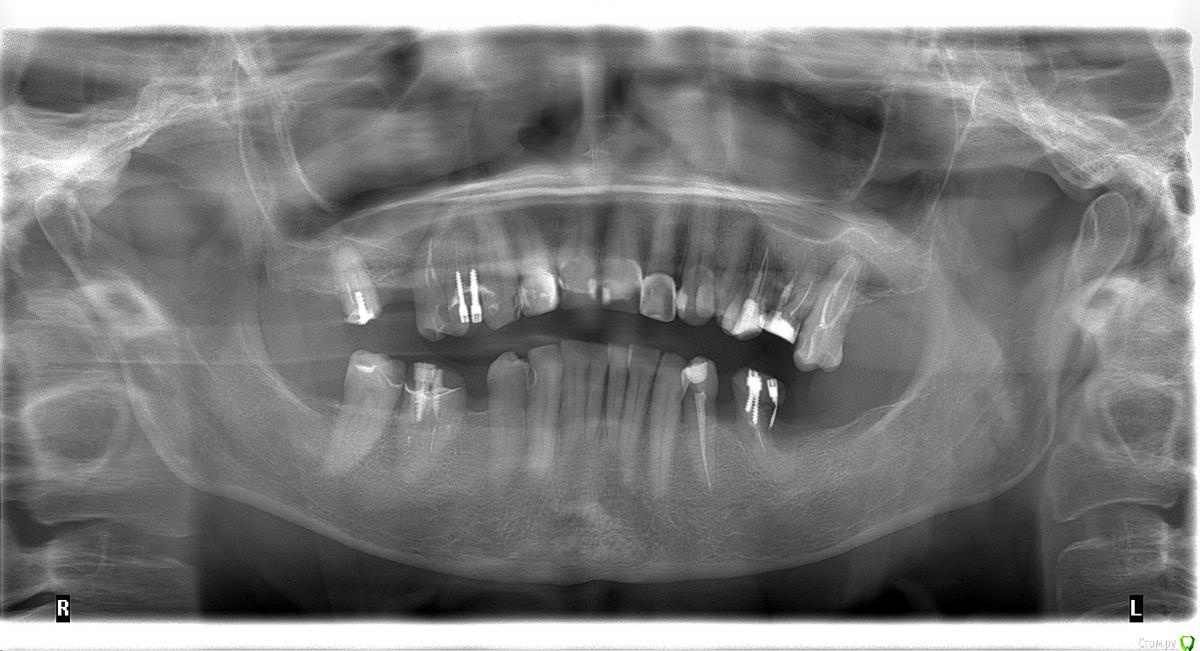

dr.Dre Опубликовано 27 июня, 2017 Поделиться Опубликовано 27 июня, 2017 Добрый день коллеги тему уже создавал но дал мало информации ,пациентка 58 лет .Помогите составить план лечения,имплантацию не потянет .Нужно ли здесь поднимать прикус? Ссылка на комментарий

Aquarius Опубликовано 27 июня, 2017 Поделиться Опубликовано 27 июня, 2017 ТРГ анализ по Риккетсу и Сассуни подскажут , можно и нужно ли поднимать прикус Ссылка на комментарий

chervoncevdaniil Опубликовано 27 июня, 2017 Поделиться Опубликовано 27 июня, 2017 ТРГ анализ по Риккетсу и Сассуни подскажут , можно и нужно ли поднимать прикусЛибо анализ Бродерика без ТРГ,но для этого модели должны быть загипсованы в артикулятор как минимум Ссылка на комментарий

chervoncevdaniil Опубликовано 27 июня, 2017 Поделиться Опубликовано 27 июня, 2017 (изменено) Ну в таком случае я не знаю как вы будете низ боковые сегменты протезировать,но 36 однозначно под удаление,26 и 27 в связи с деформацией плоскости видимо тоже придется,47 и 17 под вопросом и у нее получаются концевые дефекты.Опять же повторюсь,очень плохо видно что в боковом отделе,но настолько прикус вы навряд ли поднимете,чтобы и боковые зубы остались и при этом фронт не получился как у лошади,потому что по размерам резцы и клыки абсолютно нормальные Изменено 27 июня, 2017 пользователем chervoncevdaniil Ссылка на комментарий